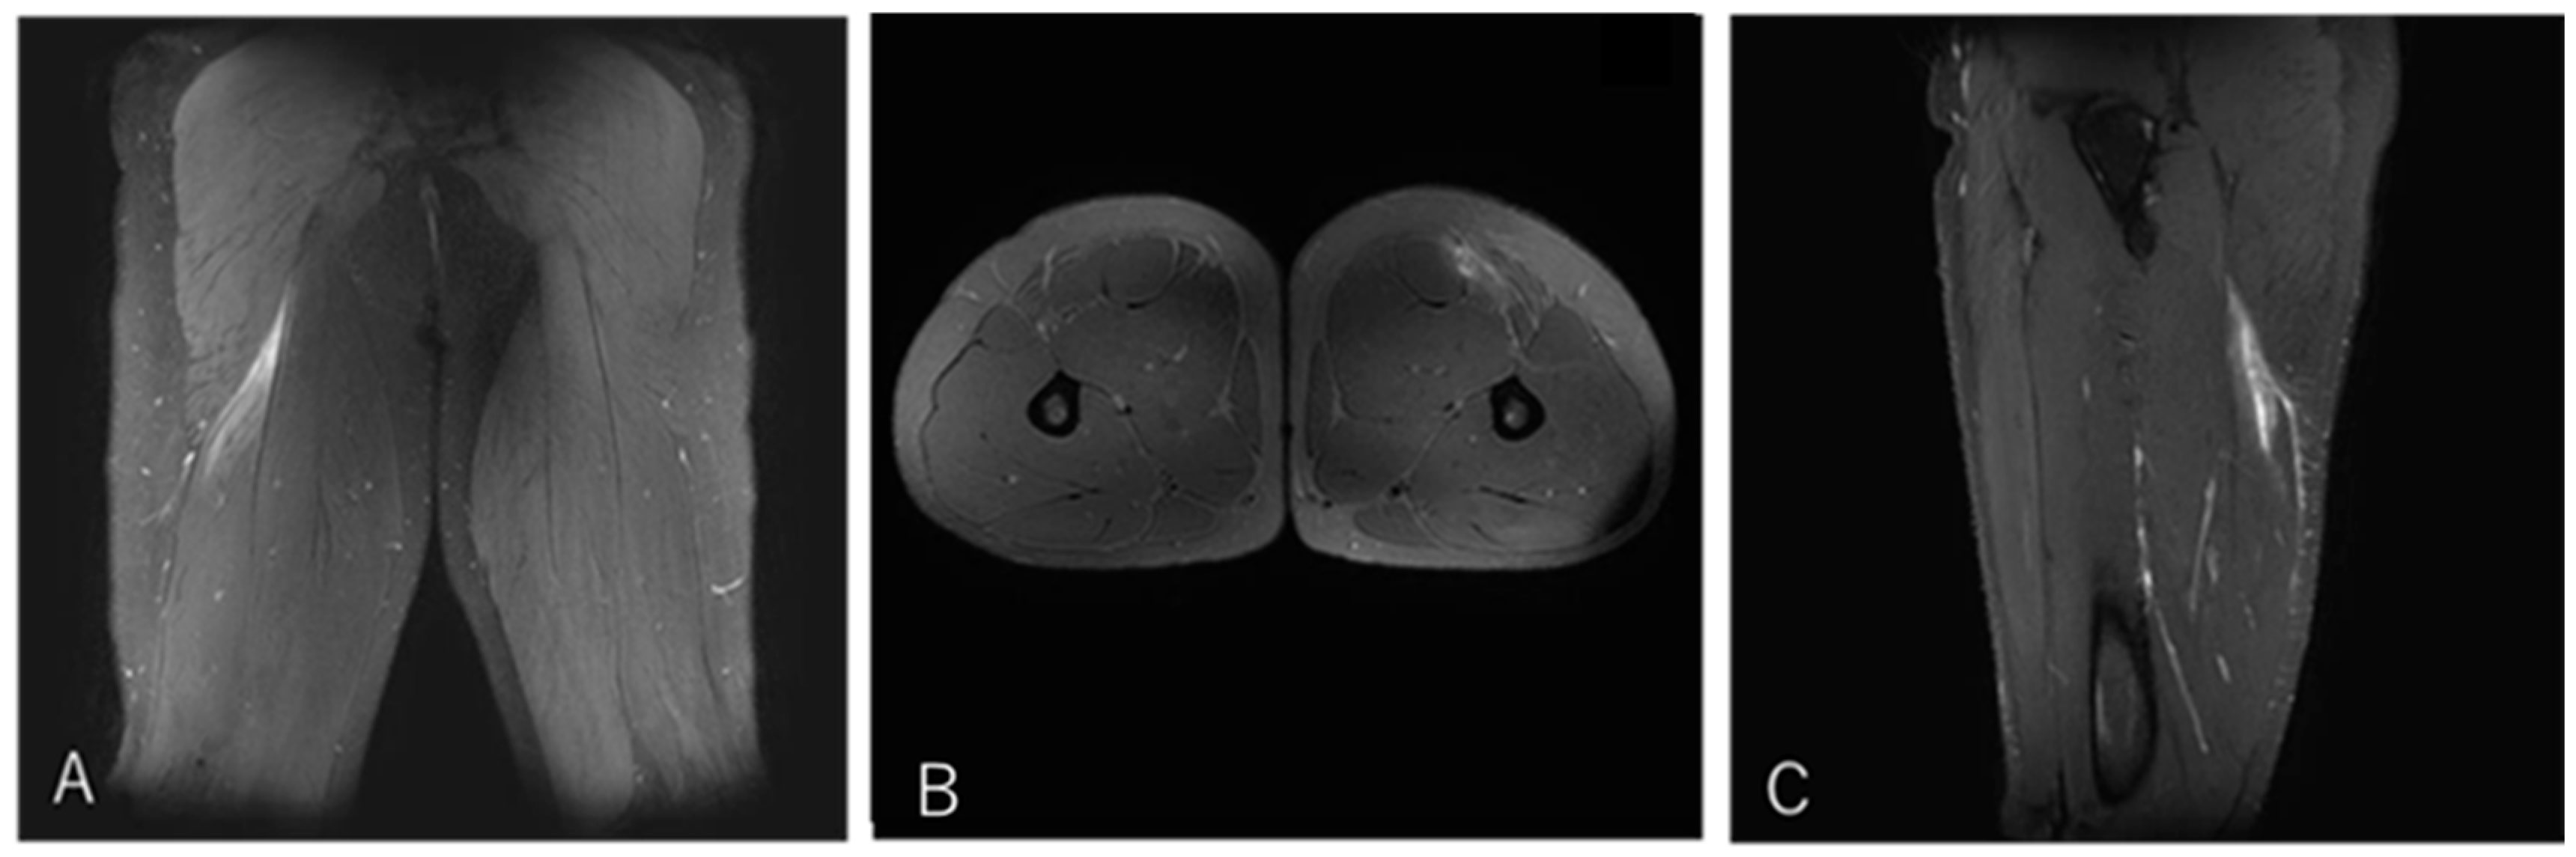

3.4.4. Case 4—Type II/Zone C (Proximal MTJ Tear), Grade 2

A 20-year-old center (BK) developed posterior thigh pain during a match while tackling an opponent. He returned to play after three weeks (Figure 7).

Figure 7. Case 4 MRI images: BFLH proximal MTJ injury, Type II. (A) (Coronal image): This is an injury to the proximal musculotendinous junction of the CT, with no evidence of tendon tortuosity. Haemorrhage is present on the BFLH side. (B) (Axial image): prone position, A haematoma is noted on the BFLH side of the CT. (C) (Sagittal image): A haematoma is observed in the cross-section of the BFLH.